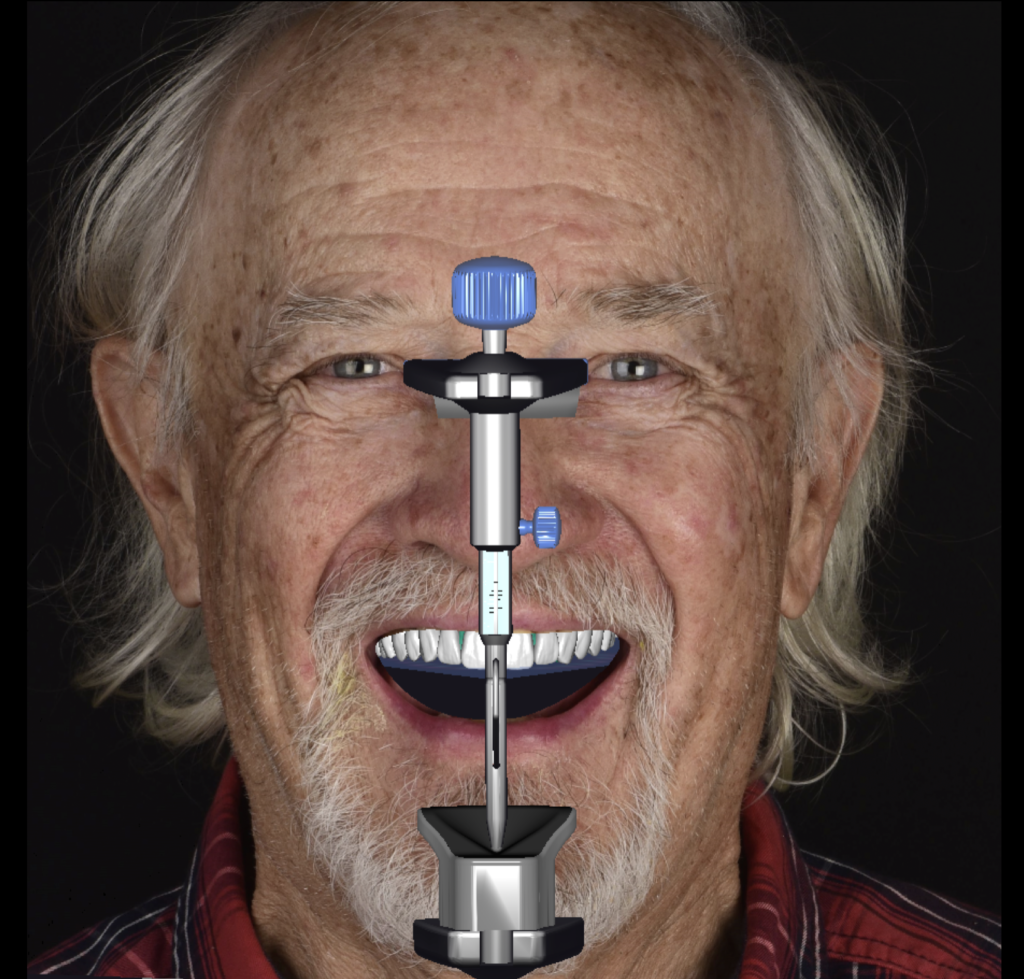

Digitalización del paciente.-Diseño de sonrisa digital.-Simulación real de sonrisa. Coronas Provisionales de Acrilico Coronas Cerámicas Total. (Sin metal) Aumento de dimensión vertical.

Procedí con el estudio de Diseño de Sonrisa para poder analizar el caso en profundidad y buscar la mejor estrategia y planificación para el paciente. Lógicamente, cuando realizamos un estudio de Diseño de Sonrisa, llevamos a cabo una simulación real en la boca del paciente para que pueda visualizar el posible resultado final antes de iniciar el tratamiento. Después de la cita para la simulación, el paciente aceptó el tratamiento, y procedimos a retirar las coronas antiguas y preparar los dientes para la colocación de coronas provisionales, que las llevó durante un par de meses. Con estas coronas provisionales, fuimos capaces de corregir, modificar y lograr la función correcta, además de mejorar la estética, y el paciente se sentía cómodo. Luego, decidimos replicar las coronas provisionales y transformarlas en restauraciones cerámicas indirectas en el laboratorio.